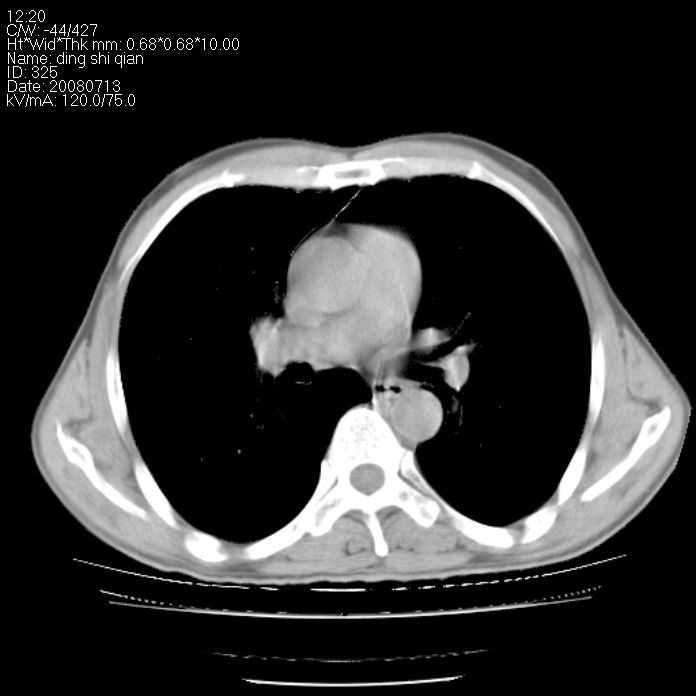

标题: CT14654:男 50岁 近来胸痛 [打印本页]

标题: CT14654:男 50岁 近来胸痛

右侧上肺块状软组织影,浅分叶,边缘毛刺证,与胸膜粘连,考虑:周围性肺癌

右侧上肺块状软组织影,浅分叶,边缘毛刺证,与胸膜粘连,考虑:周围性肺癌!支持!

以下是引用晓杰在2008-7-16 22:00:00的发言:[br]右侧上肺块状软组织影,浅分叶,边缘毛刺证,与胸膜粘连,考虑:周围性肺癌